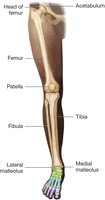

Pelvic Girdle

Ilium: Superior hip bone

Ischium: Inferior hip bone

Pubis: Anterior hip bone

All three form the acetabulum (hip socket)

Lower Extremity

Femur: Thigh bone

Tibia: Shin bone

Fibula: Thin lateral bone of the lower leg

Patella: Kneecap